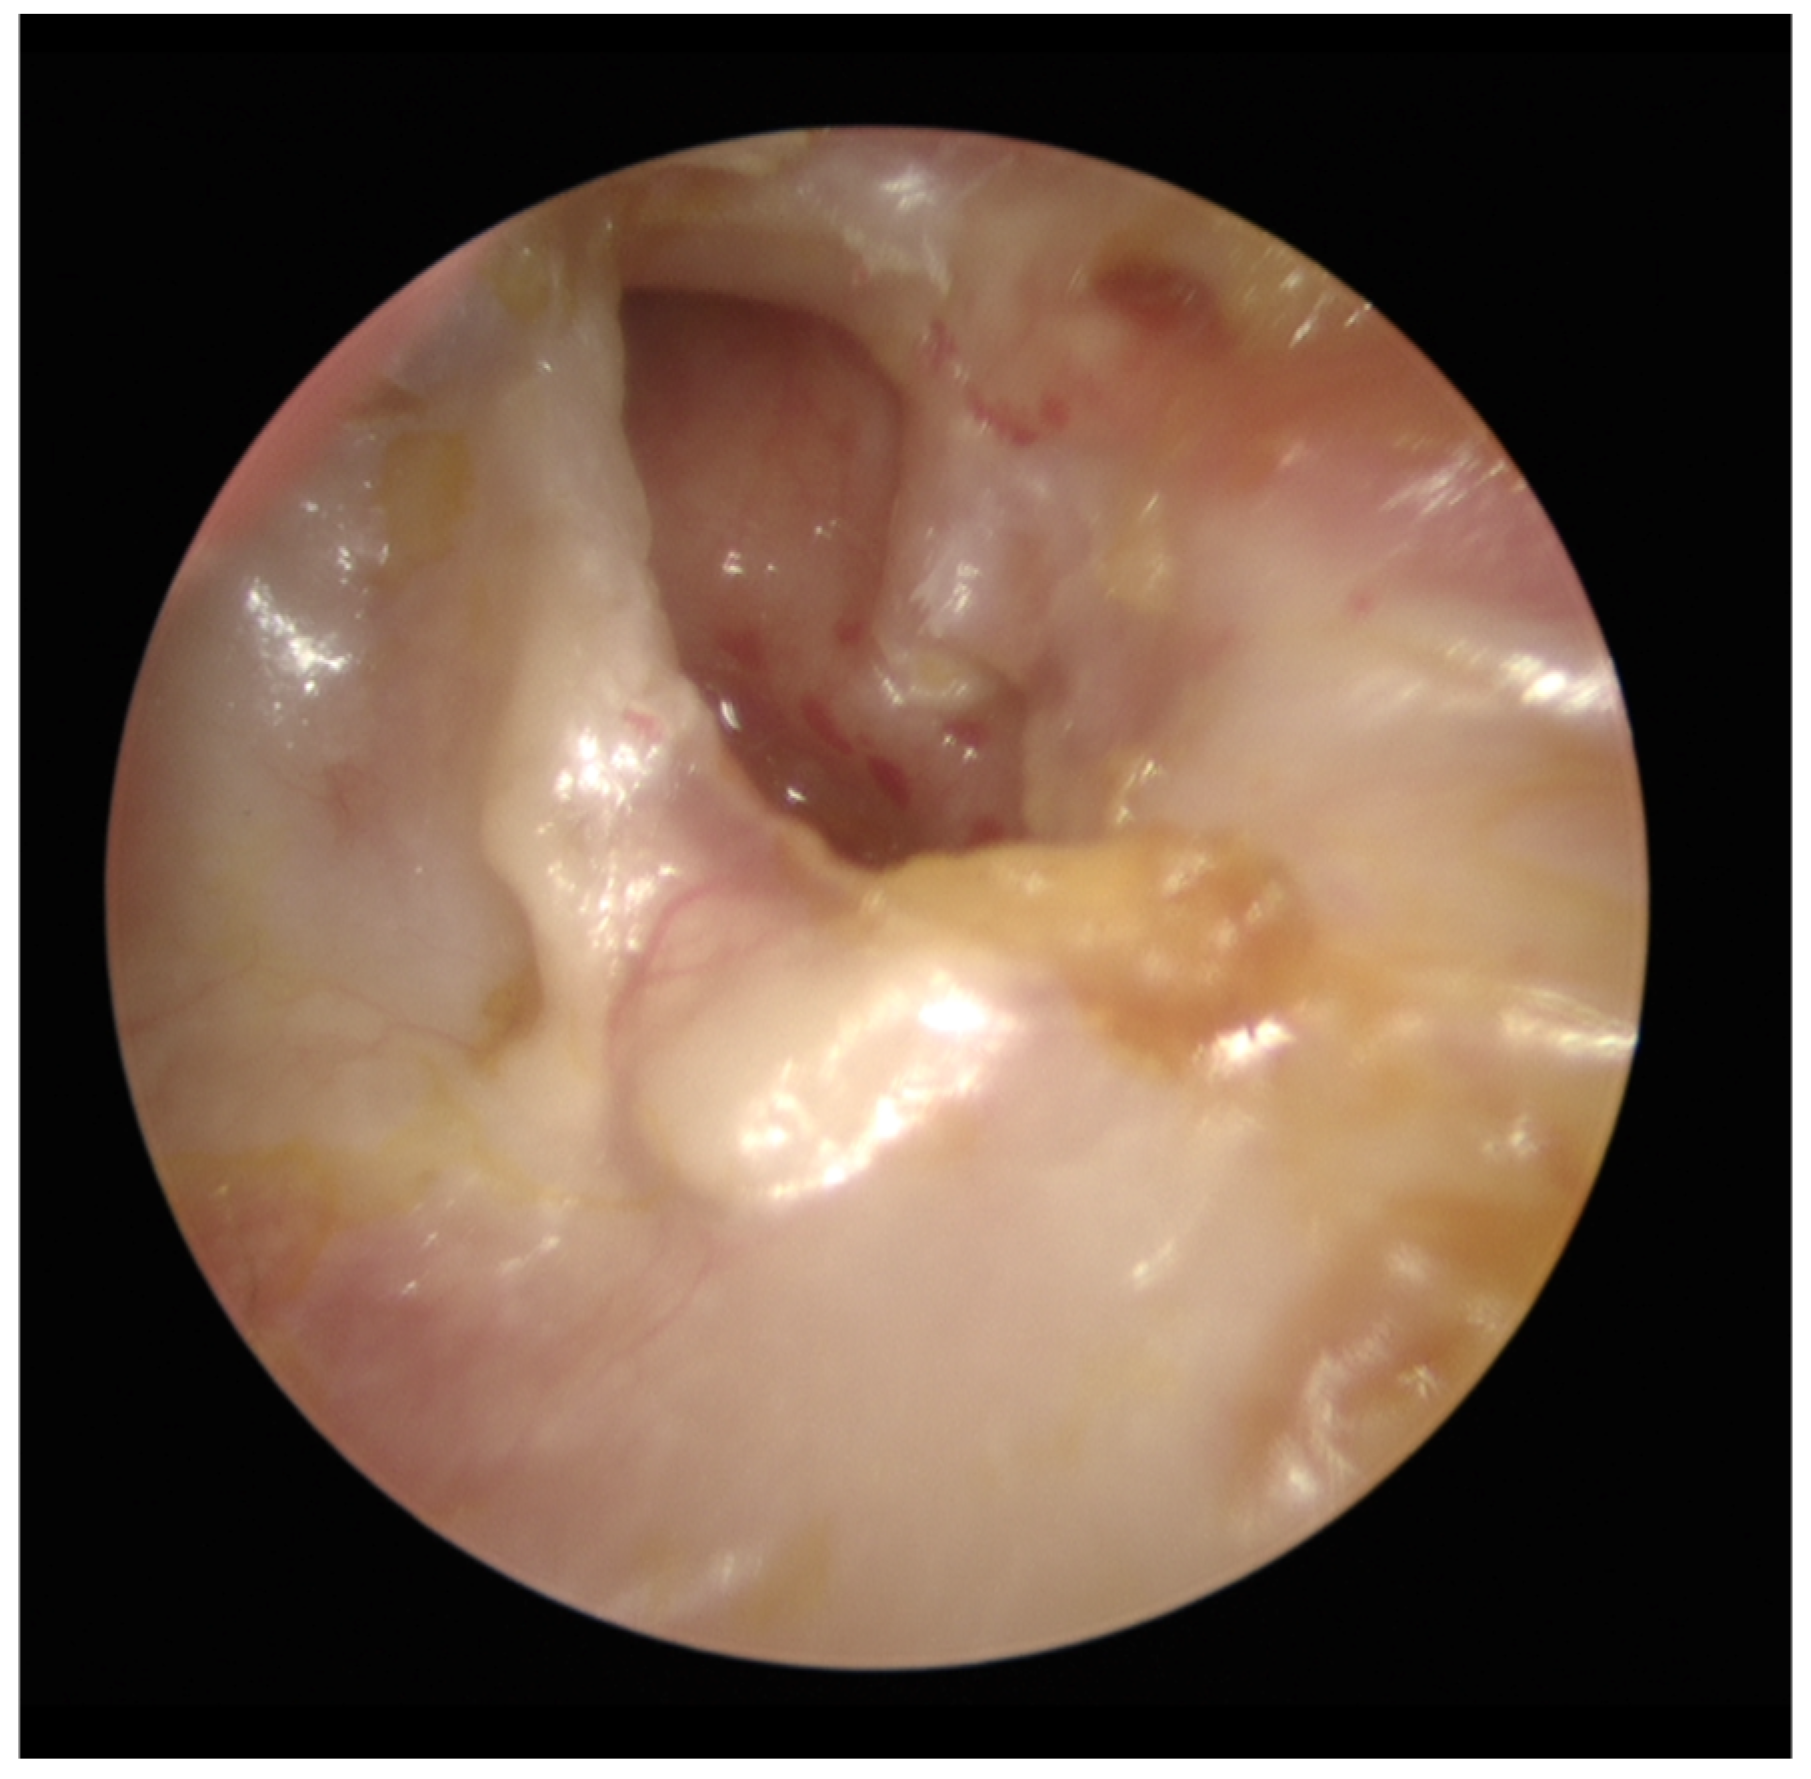

The patient was placed on the waiting list for left endoscopic tympanoplasty and ossicular chain reconstruction. At the time of the surgery, examination remained unchanged and a tympanomeatal flap was raised. There was a tiny incus remnant superiorly which was removed and no discernible malleus remnant. Stapes was within the oval window niche, not fixed and fully intact (Figure 1b). Disease extent was reasonably confined to the mesotympanum and consistent with cross sectional imaging. Keratin was fully cleared from the stapes. Curettage of the scutum and inspection of all key areas ensured all macroscopic disease had been removed. A Kurz partial ossicular chain prosthesis (PORP) was placed. The Variac system was used, and the “dummy” showed the optimal length to be 2.5mm.

Figure 1b. Endoscopic view of left tympanic membrane, tympanomeatal flap has been raised showing absent malleus and incus with stapes intact.